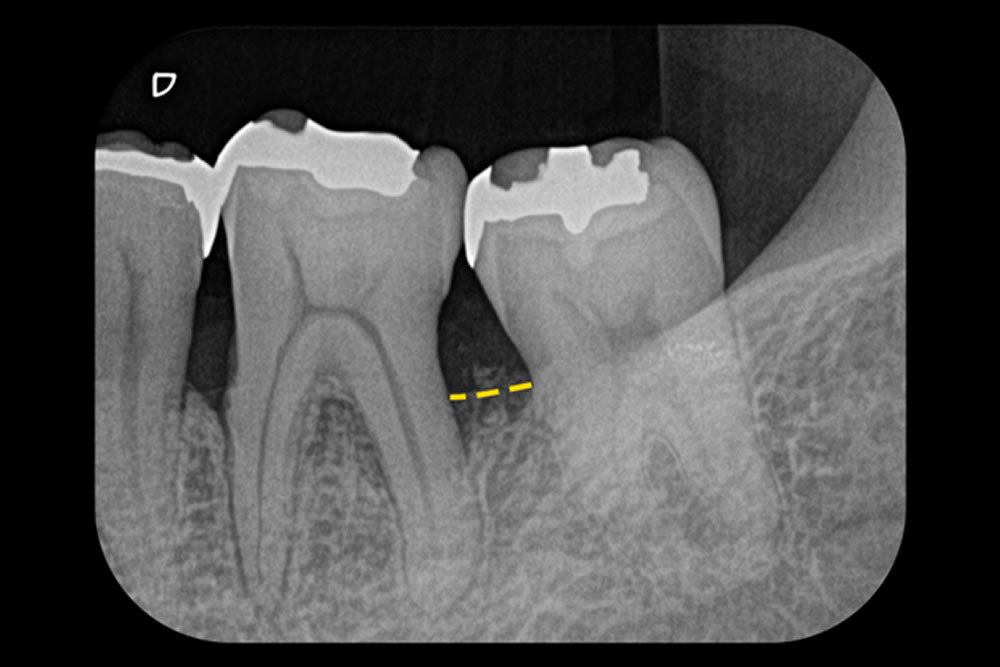

さらに、「Er-LBRT(Er:YAGレーザーを用いた骨造成手術)」を用いて、移植した骨の表面に血餅(自然なかさぶたのようなもの)を形成し、骨補填材が安定するよう処置しました。治療から4年が経過した現在も、歯と歯ぐきの状態は良好で、安定した経過を維持しています。